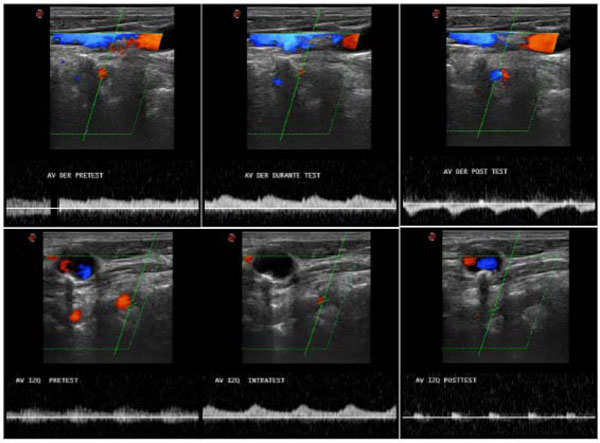

[Electronic Publication Date: December 23, 2011]P Naldi, L Collimedaglia, D Vecchio, M.G Rosso, F Perl, A Stecco, F Monaco and M.A Leone